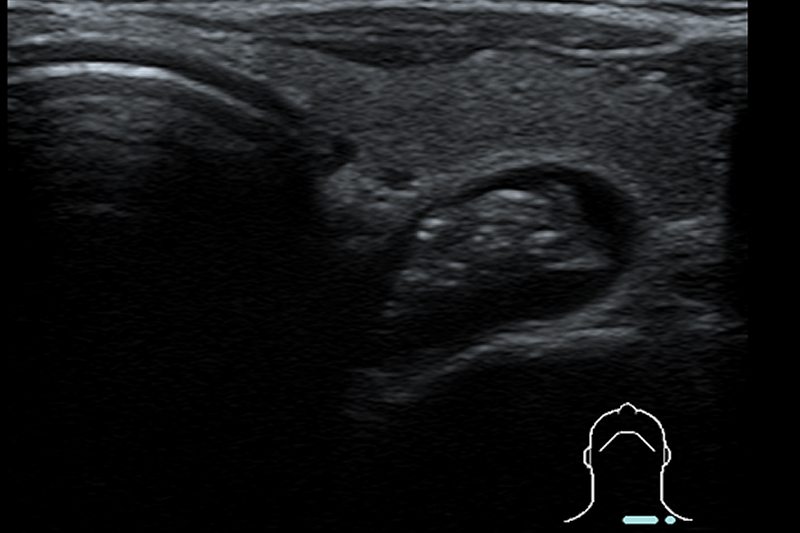

良性甲状腺腫瘍

甲状腺の画像検査としてもっとも有効なのは超音波検査です。腫瘍の大きさ、形、腫瘍内部の状態などを観察して良性か悪性かの鑑別を行います。甲状腺腫瘍の大部分は良性腫瘍であり基本的には経過観察でよいものがほとんどですが、この症例のようにサイズが大きく気管や血管、食道を圧迫している場合は手術が必要です。

頚部食道憩室

頚部食道憩室(Zenker憩室)は甲状腺腫瘍と間違われやすいので、食道との連続性の有無に留意して検査することが必要です。